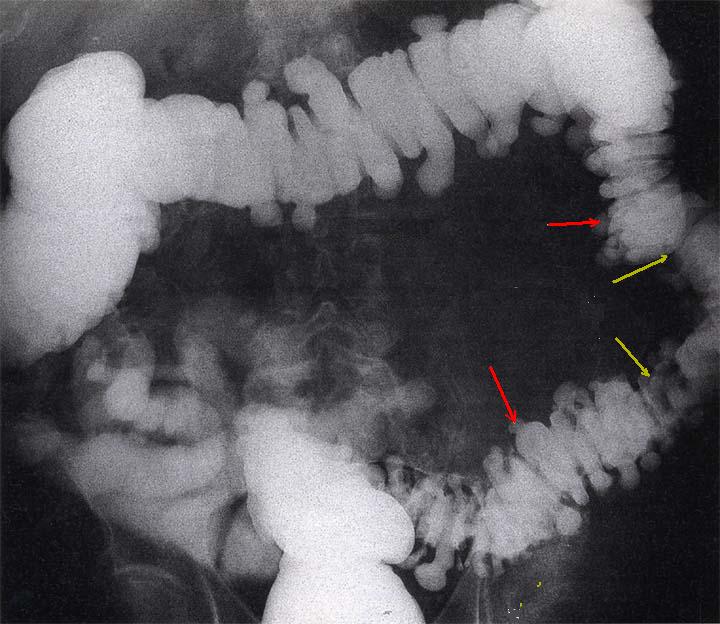

Au stade evolutive

image de ulceration marque en circumferentiel (

fleche rouge ) et deformation legere de la region

ileo caecale . Image radiologique en double de

contrast . . |